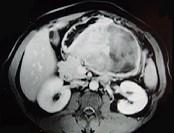

问题 男,36岁,腹胀、消化不良、消瘦、中上腹痛,影像检查如下图,最可能的诊断是 ( )

选项 A.胃间质肉瘤并肝转移 B.胃间质瘤并原发性肝癌 C.内胚窦瘤肝转移 D.胃淋巴瘤伴原发性肝癌 E.胃间质瘤并肝血管瘤

答案 A